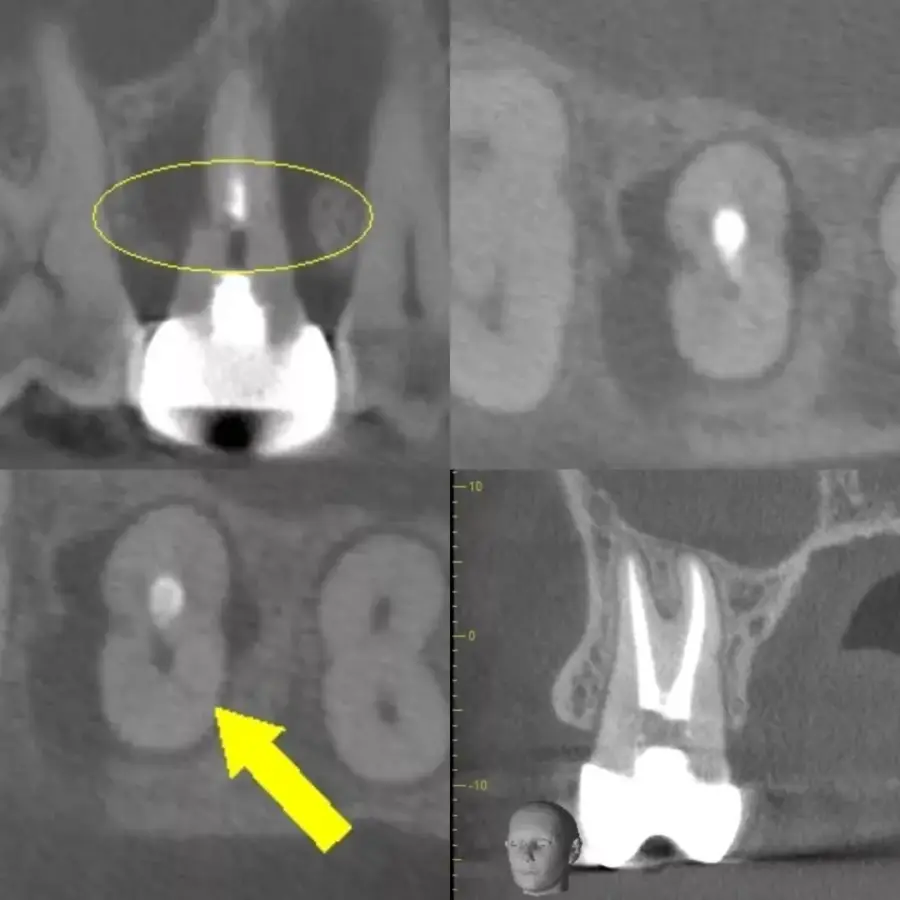

Kích thước và tính chất tổn thương

Không chỉ sự hiện diện, kích thước và đặc điểm tổn thương cũng ảnh hưởng trực tiếp đến tiên lượng. Các tổn thương nhỏ, bờ rõ và không tiêu xương lan rộng thường có khả năng lành thương tốt hơn. Ngược lại, tổn thương lớn, bờ không đều hoặc nghi ngờ dạng nang thực sự sẽ có tiên lượng dè dặt. Trong những trường hợp này, điều trị nội nha lại đơn thuần có thể không đủ. Việc đánh giá chính xác bằng CBCT giúp bác sĩ tránh đánh giá thấp mức độ bệnh lý.

Vai trò của CBCT trong đánh giá tiên lượng

CBCT cung cấp thông tin ba chiều về hệ thống ống tủy, tiêu xương, thủng và nứt chân răng. Trong retreatment, CBCT gần như trở thành tiêu chuẩn đánh giá tiên lượng. Việc chỉ dựa vào phim hai chiều có thể dẫn đến bỏ sót tổn thương quan trọng. Nhờ CBCT, bác sĩ có thể lập kế hoạch điều trị chính xác và thực tế hơn. Đây là công cụ giúp giảm rủi ro và tăng khả năng thành công dài hạn.